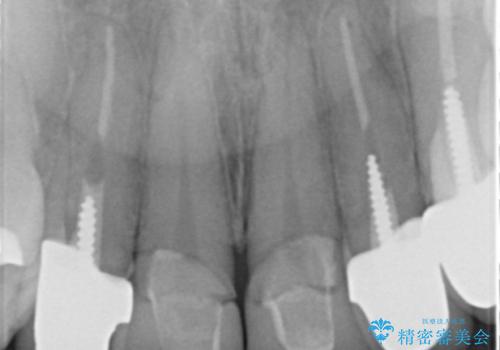

X線写真よりクラウンの際があっていない状態であることがわかり、再度精度の良いセラミッククラウンを製作していくこととなりました。

残存している歯と、クラウンの合いが悪い(不適合クラウン)歯汚れは溜まりやすく歯ぐきが腫れ虫歯・歯周病の再発リスクを高めます.